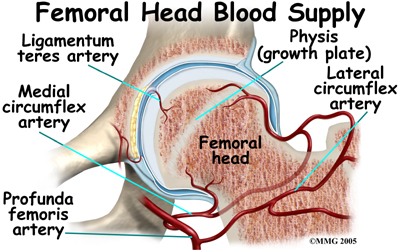

The capital femoral epiphysis is somewhat unique. It is one of the few epiphyses in the body that is inside the joint capsule. (The joint capsule is the tissue that surrounds the joint.) The blood vessels that go to the epiphysis run along the side of the femoral neck and are in danger of being torn or pinched off if something happens to the growth plate. This can result in a loss of the blood supply to the epiphysis.

Perthes disease results when the blood supply to the capital femoral epiphysis is blocked. There are many theories about what causes this problem with the blood supply, yet none have been proven. There appears to be some relationship to nutrition as children who are malnourished are more likely to develop this condition.

Children who have abnormal blood clotting (a condition called thrombophilia) may also have a higher risk of developing Perthes disease. These children have blood that clots easier and quicker than normal. This may lead to blood clotting that blocks the small arteries going to the femoral head. As a result of new evidence, the certainty of thrombophilia as a cause of Perthes is now under debate. This will remain an area of study until scientists clear up the significance of thrombophilia as a possible cause of Perthes.

Children who have abnormal blood clotting (a condition called thrombophilia) may also have a higher risk of developing Perthes disease. These children have blood that clots easier and quicker than normal. This may lead to blood clotting that blocks the small arteries going to the femoral head. As a result of new evidence, the certainty of thrombophilia as a cause of Perthes is now under debate. This will remain an area of study until scientists clear up the significance of thrombophilia as a possible cause of Perthes.

Whatever the true cause of ischemia (lack of blood to the area), the result is bone death (called necrosis) of the femoral head. Without a normal blood supply, the bone loses its strength and shape. The loss of bone density and softening of the head result in a femoral head that is misshaped. With the hip supporting the weight of the body, tiny microfractures in the soft, necrotic bone fail to heal. This is another reason why normal wear and tear results in a deformity.